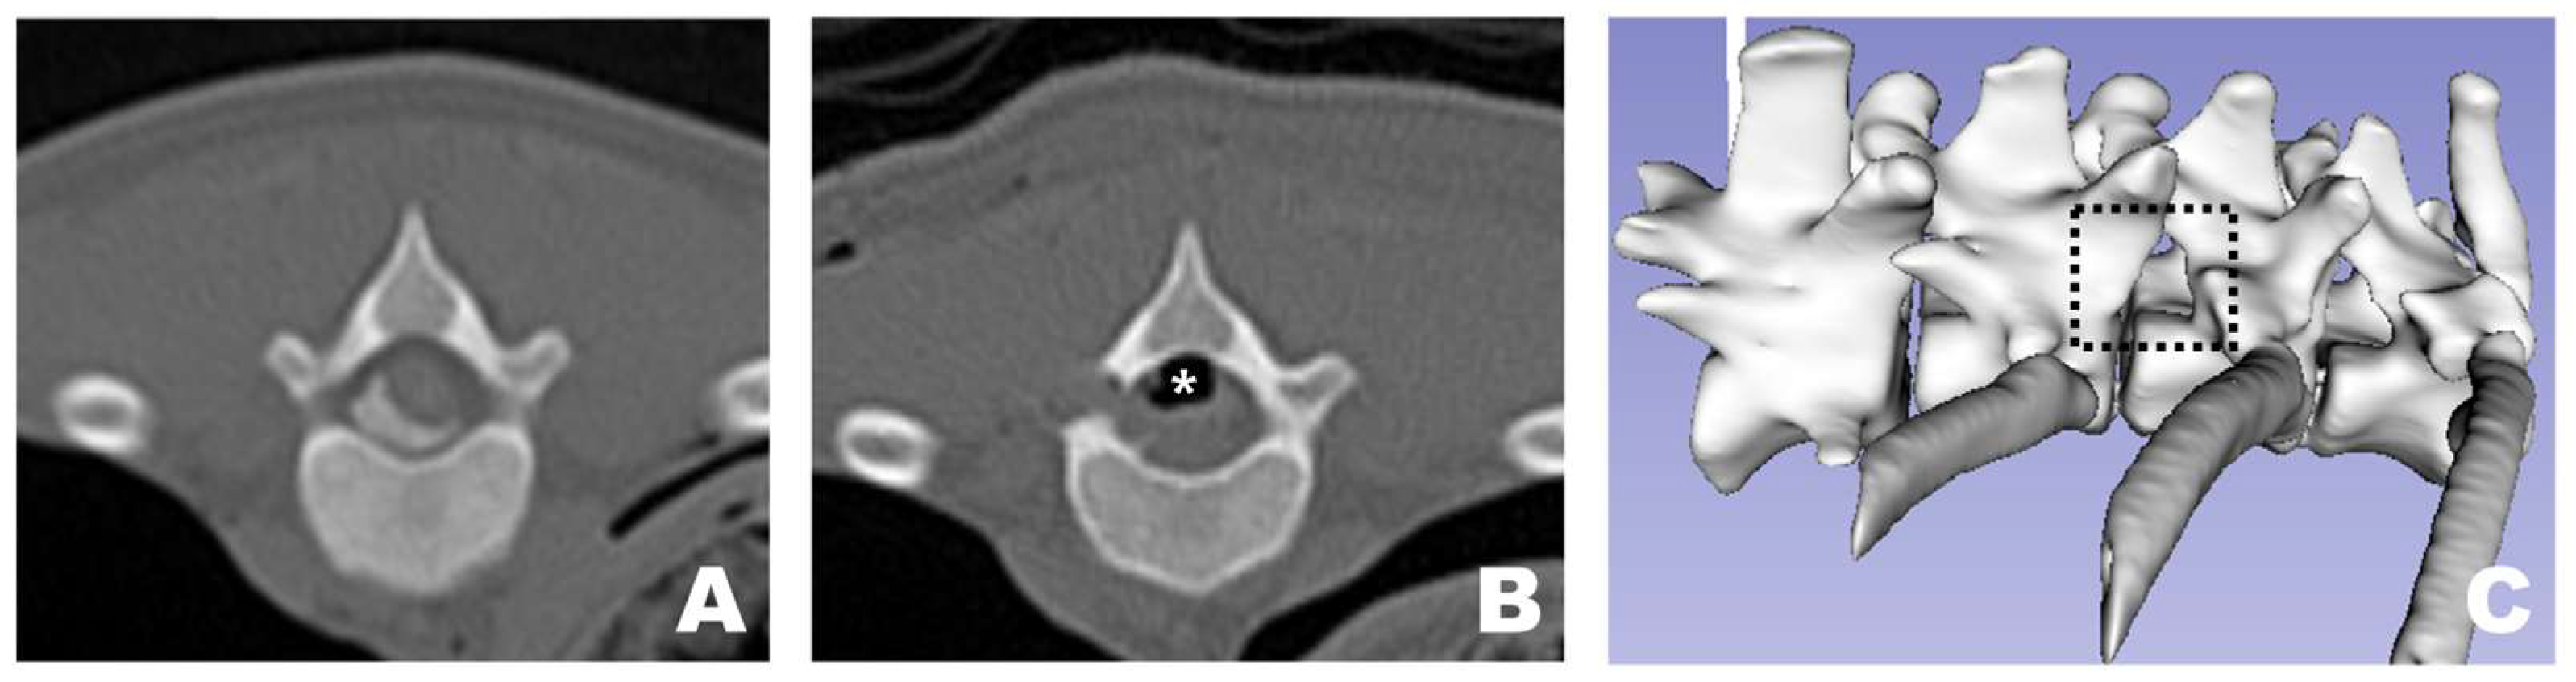

In all dogs, FDADM-MB was clearly visualized through the endoscopic view without requiring any additional incisions beyond the initial 1 cm skin incision at each portal. Following the completion of the preparatory steps, the scope was stabilized with the left hand, and disc removal was performed via the working portal. Osteotomy of the accessory process was successfully performed in all patients, as confirmed by postoperative CT imaging and 3D reconstruction (Figure 10). In two of the 13 dogs, additional osteotomy was required beyond the accessory process: the articular process (Dog 1) and vertebral body (Dog 3).

Figure 10.

Osteotomy site as observed in CT and 3D reconstruction view at the transverse view of a CT scan. (A) Pre-operative appearance with the FDADM-MB properly implemented. (B) Post-operative view showing appropriate osteotomy of the accessory process and removal of the FDADM-MB. Due to the nature of the cadaver, the air bubbles (white asterisk) formed above the spinal cord did not resolve after surgery. (C) The black dotted square highlights the area in the 3D reconstruction view where the accessory process is completely removed, clearly revealing the lateral aspect of the spinal cord.